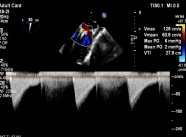

【图片6:术前超声图】

病例2为复杂功能性二尖瓣反流(FMR),术前影像提示前后瓣叶对合不良,存在明显间隙(GAP),反流程度达极重度。该类病例因瓣叶牵拉明显、张力大,是TEER技术中的典型难点。